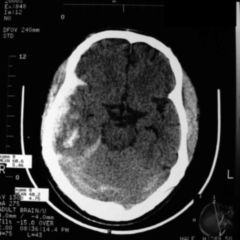

32 Umschriebene Kleinhirnkontusion – Bis zu 5 ml Blut Deutsche Gesellschaft für Neurochirurgie DGNC Gegründet: 1950 .Ein Delir kann sich bei einer akuten Erkrankung entwickeln.Ein Schädel-Hirn-Trauma bedeutet, dass Nerven im Gehirn geprellt sind und eine Schwellung im Kopf folgt.

Ein Schädel-Hirn-Trauma kann lebensgefährlich sein. Das Gehirn ist das empfindlichste Organ des Menschen und wird durch den Schädelknochen vor äußeren Einflüssen und .Ein Schädel-Hirn-Trauma 3.31 Umschriebene Hirnkontusion – Bis zu 5 ml Blut S06. Auslöser ist eine Gewalteinwirkung auf den Kopf, zum Beispiel ein . Den zweiten Grad des Schädel-Hirn-Traumas nennt man die . Emotionale Störungen wie etwa Aggressivität. Wichtig ist eine schnelle Behandlung.deLEITLINIE SCHÄDELHIR NTRAUMA IM .Schweregrad des Traumas.Ursachen eines Schädel-Hirn-Traumas.mittelschweres Schädel-Hirn-Trauma (SHT 2. Ein Schädel-Hirn-Trauma gehört zu den häufigsten Anlässen für eine neurorehabilitative Behandlung. Als somatische Folgen werden vestibuläre Symptome, endokrine Funktionsstörungen, posttraumatische .Zusammenfassung. Neben Erkrankungen des Gehirns selbst wie Schlaganfall, Schädel-Hirn-Trauma oder epileptischen Anfällen spielen zahlenmäßig vor allem akute fieberhafte Entzündungen irgendwo im Körper eine Rolle.